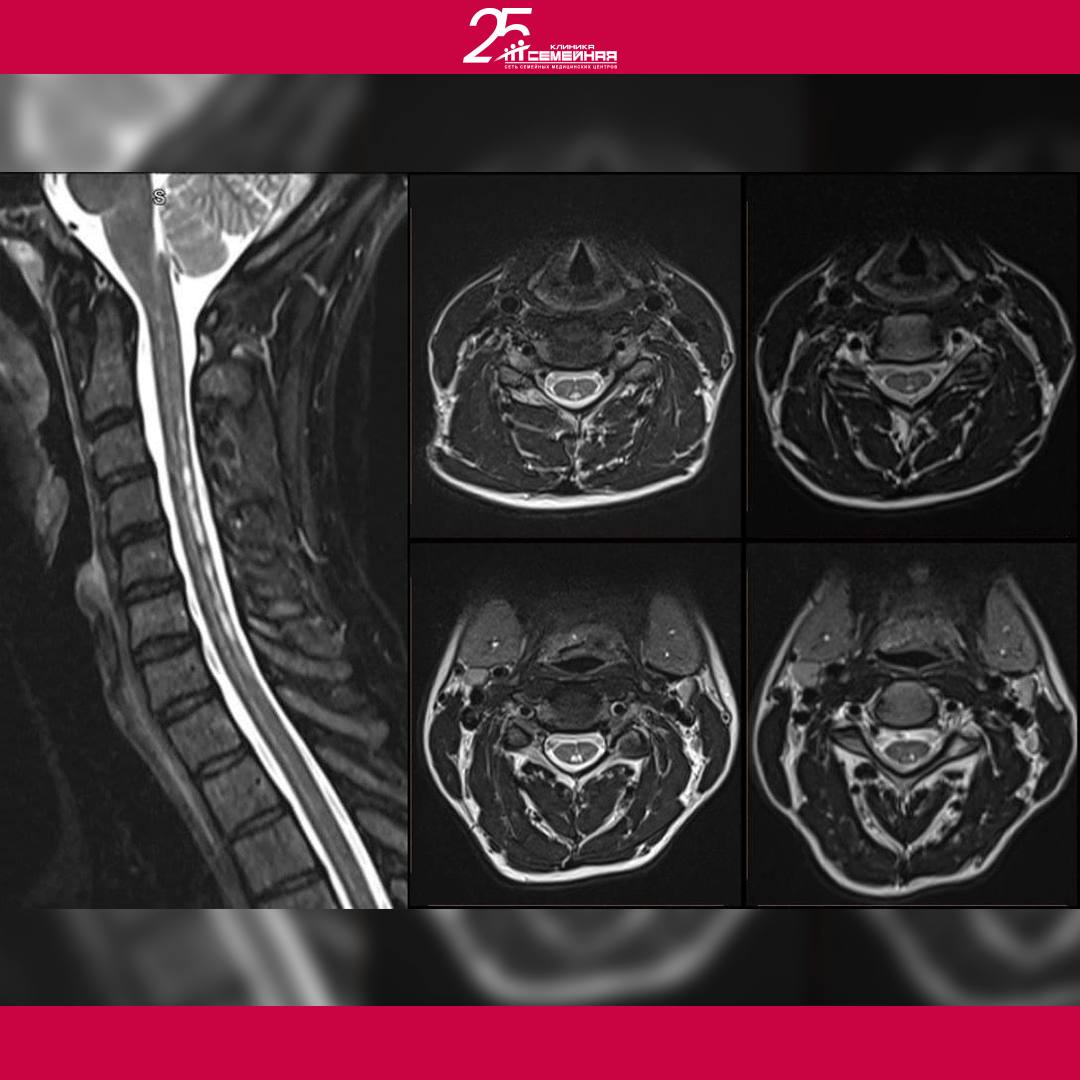

В связи с этими жалобами пациентка самостоятельно выполняет МРТ шейного отдела позвоночника, на котором якобы обнаруживается сирингомиелия в шейном отделе спинного мозга.

• Начало лета 2020 года − повторное плановое МРТ, по которому врач-радиолог высказывает предположение о миелопатии.

• На МРТ изменений не наблюдается несмотря на клиническую ремиссию у пациентки.